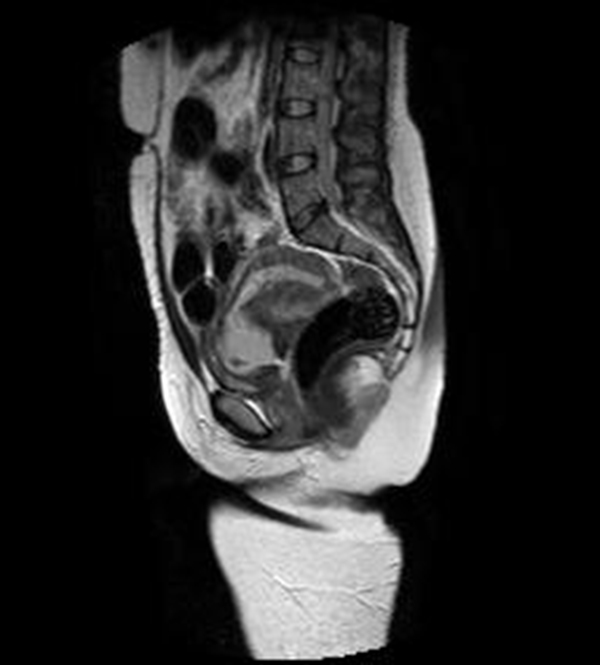

Se realizó una RNM (Philips 1.5 Tesla) que permitió confirmar el diagnóstico de EEC (figuras 5 a 8).

Figura 5A Imágenes sagitales de RMN potenciadas en T2 (TR: 1540 TE: 70) y T2 de disparo único (TR: 709 TE: 315) que muestran el saco gestacional hiperintenso localizado en el canal cervical y con tejido fetoplacentario en su interior, más evidente en la imagen B. Nótese que los orificios cervicales interno y externo se encuentran cerrados

Figura 5B Imágenes sagitales de RMN potenciadas en T2 (TR: 1540 TE: 70) y T2 de disparo único (TR: 709 TE: 315) que muestran el saco gestacional hiperintenso localizado en el canal cervical y con tejido fetoplacentario en su interior, más evidente en la imagen B. Nótese que los orificios cervicales interno y externo se encuentran cerrados